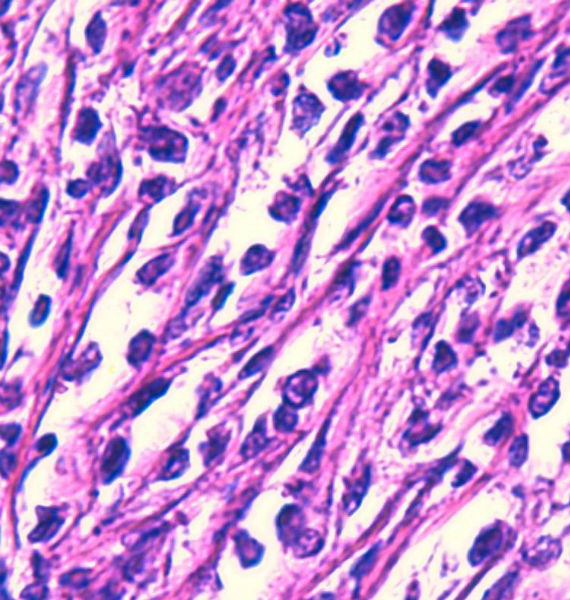

免疫组化染色:CA125(-),PLAP(-),NSE灶状阳性,Vimentin(+),a-inhibin(-),CK7(-),CK20(-),CD15(-),PSA(-),S100(-),MyoD1(-),CD38(-),CD56(-),HMB45(-),CK8(-),NF(-),CGA(-),syn(+),MPO散在(+)可能是炎细胞吧,LCA(+),CD133(+).

好的HE切片和准确可靠的免疫组化结果是淋巴瘤等较难病例病理诊断的基础。本例从HE来看不太像典型的淋巴瘤或癌,免疫组化就很重要了,但本例组化结果之间似乎不易解释:

1.syn与LCA等淋巴系标记的阳性判断,镜下须观察阳性细胞是否一致,是相同的细胞还是不同的细胞等

2.如果考虑淋巴瘤,B系的标记如CD20和PAX5结果也不太一致,另外CD133+究竟如何也有待探讨,好像楼主未显示其图片

3.ALK等也不太确切,

不知楼主以上的组化结果阴阳性对照如何?我个人经验不足,不敢妄下结论,但认为诊断淋巴瘤(弥漫大B,或间变淋巴瘤)可能会有风险。

今天又做了免疫组化,请大家帮看看。CD10(-),CD138(-),CDX2(-),CD3(-),CyclinD1(-),CD2(-),CD117(-),CD7(-),CD30(-),CD23(-);CD20强(+),BCL-2,Bcl-6,EMA,PAX-5,MUM-1,CD5,ALK,CD68都是散在阳性,大家帮确定一下是否阳性。B细胞淋巴瘤可以确定了,不知是哪种类型的?

是的,syn(+),LCA(+), CD79a阳性, CD3阴性,NSE是局部胞核,胞浆着色,主要是胞浆着色;SYN也是局部,主要是胞核着色,胞浆很少。不对吗?我也迷糊。也许我看错了,不像那种典型的胞浆颗粒状着色。大家帮看一看。